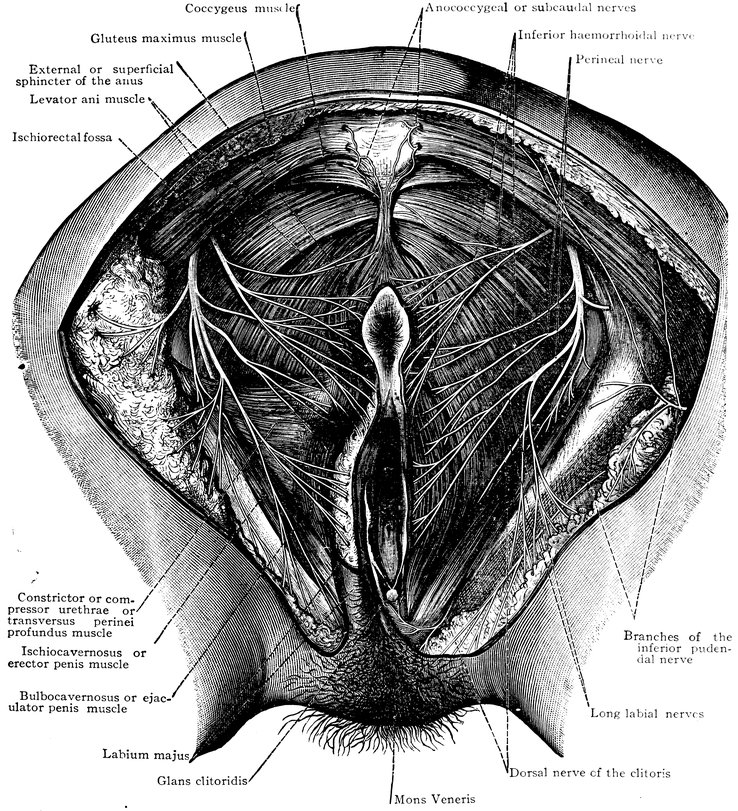

Fig. 3.—The distribution of the pudic nerve, n. pudendus, in the female perineal and pubic regions. The trunk of the pubic nerve, n. pudendus, is covered by the gluteus maximus muscle. On the right side of the body the branches of the inferior pudendal nerve, rami perineales, nervi cutanei fermoris posterioris have been dissected out; but the branches of this nerve to the labium majus have been cut short. The formation of the anococcygeal or subcaudal nerves, nn. anococcygei, out of the posterior primary division of the coccygeal nerve and out of the perforating branches which arise from the anterior primary divisions of the fourth and fifth sacral nerves and the coccygeal nerve. (From Toldt: Atlas of Human Anatomy.—Rebman Company, New York.)